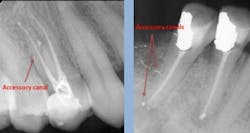

The single most important factor for predictable root canals is irrigation. Copious irrigation after every file is a must. Instrumentation is not nearly as important as good irrigation. A file cannot reach every aspect of many canals to remove all of their nerve tissue. The key to removing tissue from accessory canals is irrigation. Irrigation will dissolve soft tissue and destroy the bacteria inside the tooth that’s hidden within accessory canals. I will usually go through at least 25 cc of sodium hypochlorite (five syringes of 5 cc each) for every RCT + 5 cc of EDTA + 5 cc of 2% chlorhexidine).

Using a pumping motion and adding additional sealer ensures that voids within the canals get filled. This generates the “puff” effect with small amount of sealer being extruded from the apex of canals. It also helps ensure accessory canals are not left unfilled.